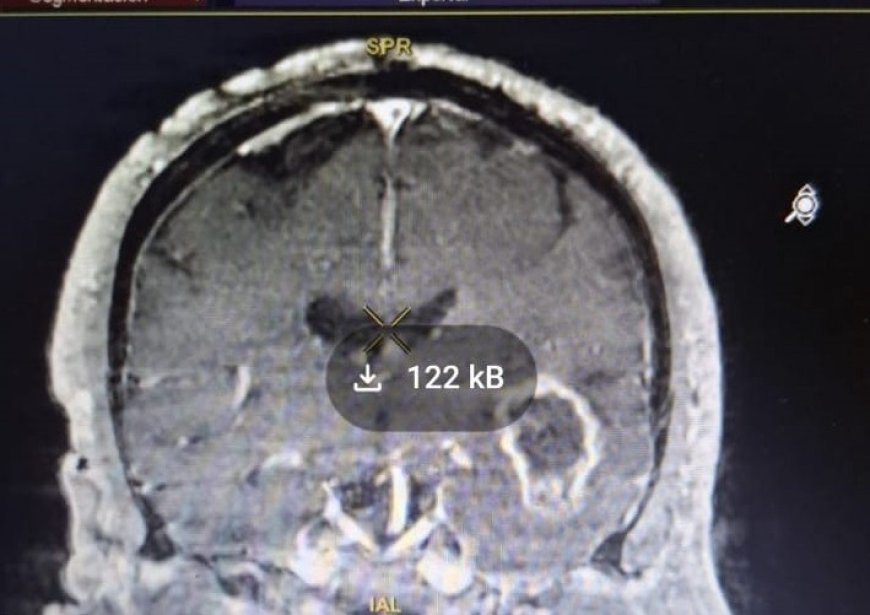

El paciente, de 57 años, presentaba un tumor maligno. Tras la intervención, se realizó una resonancia para evaluar la extensión de la resección.